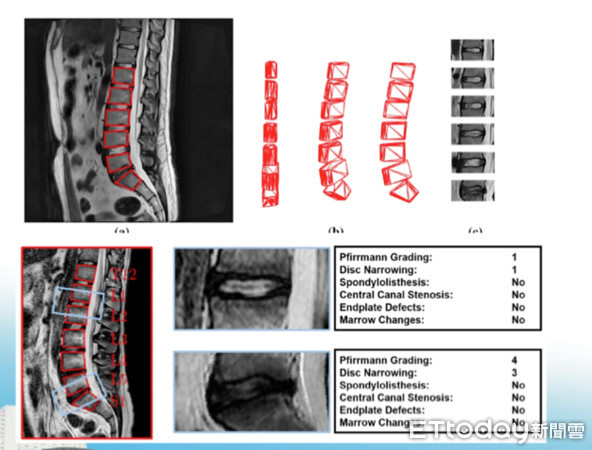

▲AI自動判讀MRI影像中的腰椎椎間盤退化程度。(圖/周伯鑫醫師提供)